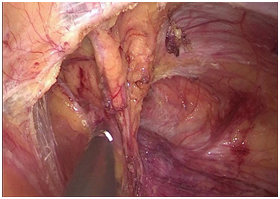

手术图片

腹腔镜直肠癌根治术

腹腔镜胃癌根治术

腹腔镜结肠癌根治术。